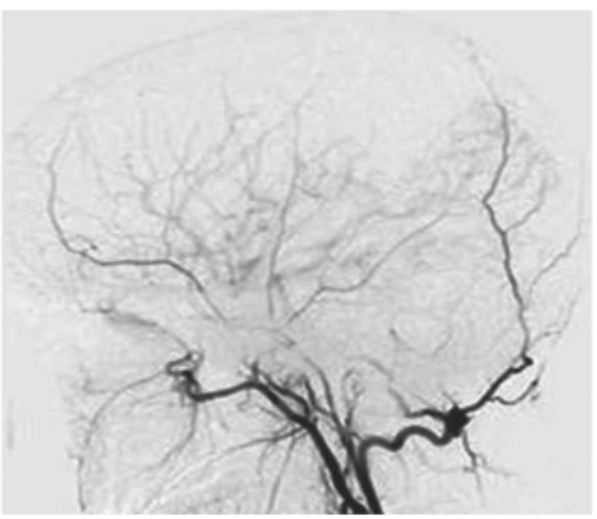

- 증상이 반복되면 수술적 치료를 고려하며, 뇌에 공급하는 혈류를 증가시키기 위해 막힌 혈관을 정상 혈관과 이어주는 혈관 문합술을 하게 됩니다.

- 모야모야병은 양쪽 뇌혈관이 대칭적으로 동시에 발생하기 때문에 한쪽 수술을 진행하고 2~4개월 후 뇌기능과 뇌혈관 검사를 해서 2차 수술을 진행합니다.